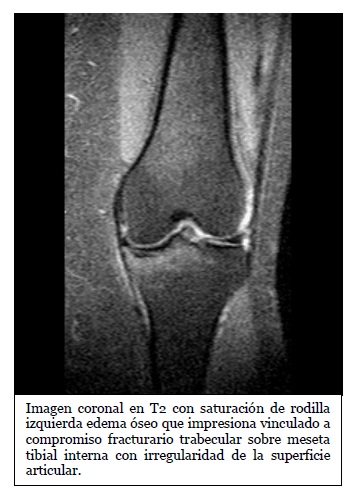

Imagen coronal de secuencia potenciada en T2 con saturación grasa de la rodilla derecha en paciente con lesión por traumatismo en valgo. Edema óseo en la

Fuente: https://epos.myesr.org/posterimage/esr/seram2014/124014/mediagallery/577012